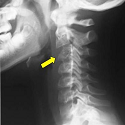

Eosinophilic granuloma of the cervical spine manifesting as torticollis in a child

Ali Akhaddar, Mohamed Boucetta

PAMJ. 2014; 19: 36. Published 16 September 2014